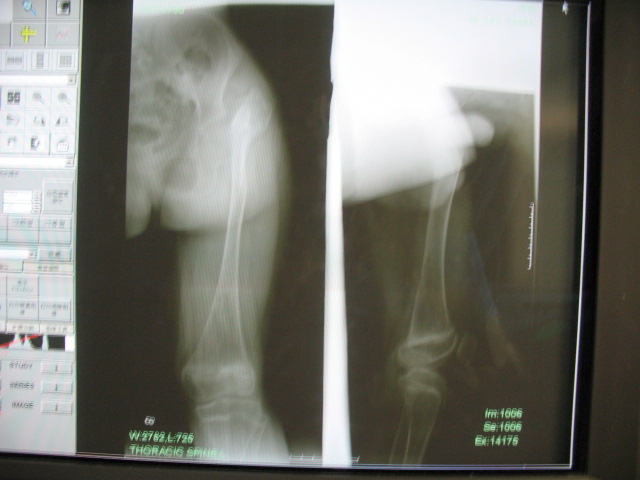

标题: PED0296:男,14岁,身材矮小,全身多处多次骨折 [打印本页]

标题: PED0296:男,14岁,身材矮小,全身多处多次骨折

骨干细而骨端膨大,多发性骨折,临床上可有典型蓝色巩膜、进行性耳聋、脆骨/三联症

成骨不全伴左髋关节脱位。成骨不全是侏儒的病因之一。[url][/url]http://www.radida.com/radinet/read.php?tid=27242

支持成骨不全,细长型

考虑:成骨不全伴左髋关节脱位。